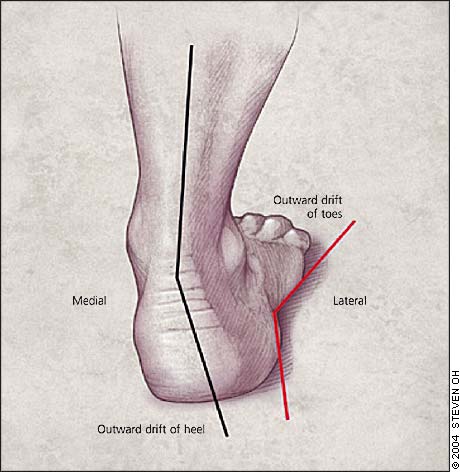

Heel Raise Exercise Progressions My Rehab Connection discount, Piezogenic papules Wikipedia discount, Achilles Tendinitis OrthoInfo AAOS discount, Bilateral calcaneal apophysitis Radiology Case Radiopaedia discount, duet with followtheeve No those are not tumors and vast majority are asymptomatic. toppodiatry podiatry whatisthat normal discount, Plantar fasciitis Symptoms and causes Mayo Clinic discount, OrthoDx Bilateral Painful Feet Clinical Advisor discount, Stretches for Heel Pain by Sydney Heel Pain Clinic discount, Bilateral Piezogenic Papules of the Heel A Comprehensive Understanding CE Foot Ankle Clinic Nashville discount, A 31 y.o. male comes in with bilateral heel pain. His xray is shown below WashU EM Blog discount, Plantar Heel Pain Physiopedia discount, Diagnosing Heel Pain in Adults AAFP discount, Calcaneus Fracture Broken Heel Bone Orthopaedic Trauma Association OTA discount, Managing the patient with heel pain British Journal of Hospital Medicine discount, How to Secure a VA Rating for Bilateral Heel Spurs discount, What is Plantar Fasciitis Causes Symptoms Treatment discount, Bilateral heel with right sided calcaneal spur. Normal plantar fascia. Download Scientific Diagram discount, Posterior heel pain Chelsea and Westminster Hospital NHS Foundation Trust discount, A Bilateral masses on the patient s Achilles tendons. B C Ankle MRI. Download Scientific Diagram discount, Heel Pain causes and treatment plantar fasciitis diagnosis and treatment discount, Pain In The Back Of The Heel What Could It Mean discount, Standing Bilateral Heel Raises discount, Bilateral broken calcaneal spurs BMJ Case Reports discount, Standing Bilateral Heel Raises discount, Exercise Bilateral Heel Raise with Eversion discount, Diagnosing Heel Pain in Adults AAFP discount, Plantar fasciitis treatment symptoms and causes healthdirect discount, Bilateral heel raises 1 year after right Achilles tendon removal. Download Scientific Diagram discount, Heel Pain Diagnosis and Management AAFP discount, Diagnosing Heel Pain in Adults AAFP discount, Radiological investigation shows bilateral heel spurs A X ray of the. Download Scientific Diagram discount, X Ray Bilateral Heel AP View and Lateral Test Price in Delhi Ganesh Diagnostic discount, Bilateral Heel Drop by Joshua Feinberg Exercise How to Skimble discount, Heel Pain Causes Treatments and Home Remedies Heel That Pain discount, Appearance 1.5 years after surgery. A Bilateral heels are preserved. B. Download Scientific Diagram discount, Product Info: Bilateral heels discount.